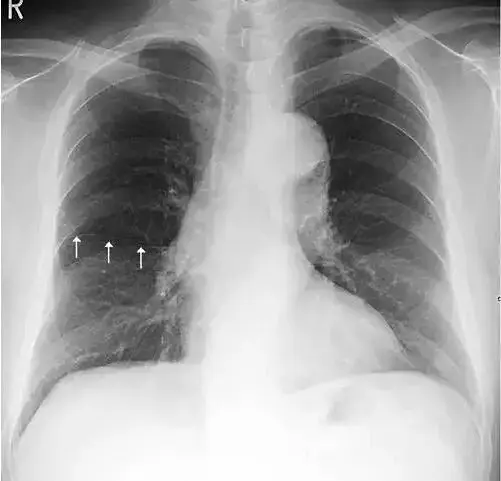

女性,24岁 轻微咳嗽3天

正常女性胸片 乳房影

肺野的划分在正常时,下肺野纹理比上肺野多而粗,而右下肺野肺纹理比左